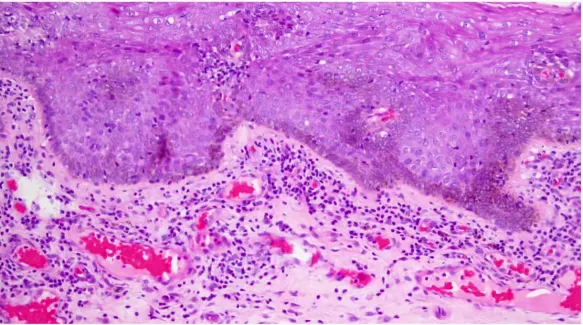

那么由于基底膜被破坏,表皮和真皮的纤维之间链接关系变得非常松散,所以表皮部分特别容易脱落,所以我们制定过程当中,经常会上去了,高倍给大家看

所以,周老师前面已经解释在这类病变当中,它的基底层细胞数量会减少,基底层结构模糊被破坏,有一些水肿,鳞状上皮的数量排列总体改变为萎缩性改变,细胞之间链接也变得模糊,加上炎症细胞带,及胶原化板块形成。这时候只能组织胶原继续往下延伸,没有办法消除现有的胶原。